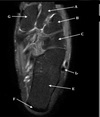

(178 cards)

1

What is letter A?

SUPRASPINATUS TENDON

2

What is letter B?

ACROMION

3

5

What is letter C?

INFRASPINATUS MUSCLE

6

What is letter D?

7

SUBSCAPULARIS MUSCLE

8

16

17

18

DELTOID MUSCLE

19

SPINE OF SCAPULA

20

21

INFRASPINATUS TENDON

22

23

24

GLENOID

25

SUPRASPINATUS MUSCLE

26

27

What is letter E?

28

GREATER TUBEROSITY

29

What is letter G

SCAPULA

30

CLAVICLE

31

AC JOINT

32

33

BICEPS TENDON

34

35

STERNOCLAVICULAR JOINT

36

STERNAL NOTCH

37

VERTEBRAL BODY

38

RT LUNG

39

What is letter F?

40

HUMERAL HEAD

41

42

43

44

STERNUM

45

CORACOID PROCESS